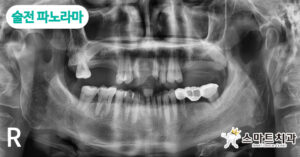

술전 파노라마 사진입니다. 상악에는 앞니 2개를 제외한 나머지 치아들이 동요도(치아 흔들림)가 없어 임플란트 식립을 권유 드렸으며, 상악동 뼈이식을 동반한 식립 계획을 설명해 드렸습니다.

치아를 상실한 채로 오랜 시간이 지나거나 치주질 환이 심한 경우, 또는 틀니를 장기간 착용한 경우라면 치조골이 흡수되어 잇몸뼈의 양이 부족해지는데요, 먼저 뼈 이식을 진행한 다음 인공치근을 식립해야 안정적으로 고정될 수 있습니다. 본 환자분께서는 상악동을 감싸고 있는 막을 들어 올려 생겨난 빈 공간에 임플란트를 식립할 수 있도록 상악동 거상술을 동반한 뼈 이식을 진행하기로 했습니다.

하악 우측 제1대구치는 충치로 인해 시큰함을 호소하시어 신경치.료를 계획하고, 하악 좌측 제2소구치~제2대구치 브릿지의 경우에는 제2대구치 염증으로 인해 브릿지 철거 후 제2소구치는 크라운 보철치.료를 하고, 제1,2대구치는 임플란트를 식립하기로 계획을 수립하였습니다.